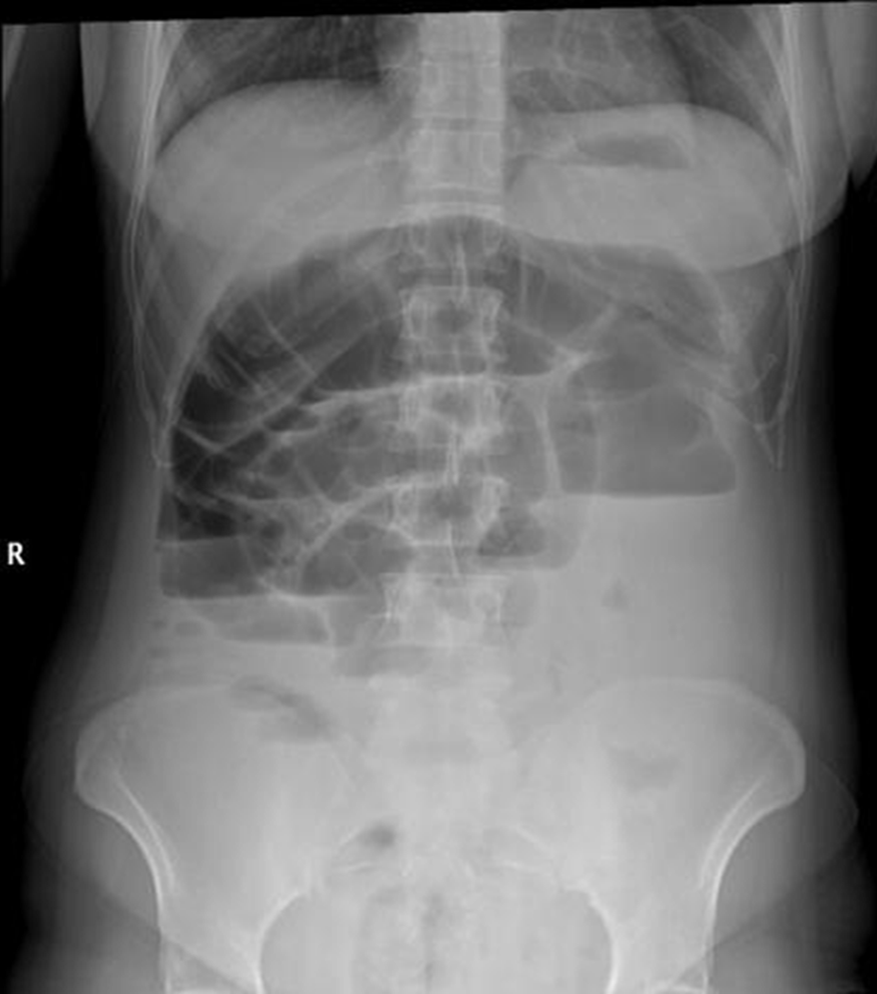

patient w/ bowel obstruction

what is this an image of?

bowel obstruction

partial or full blockage of large or small bowel that does not allow substances to pass through

idiopathic, mechanical, ileus

what are the causes of bowel obstructions?

mechanical bowel obstruction

a physical blockage

surgical adhesions, tumors

what are exmaples of a mechanical bowel obstruction?

(adynamic) ileus bowel obstruction

peristalsis stops

depending on blockage

may need to increase/decrease

what are the techniques for a patient w/ a bowel obstruction?